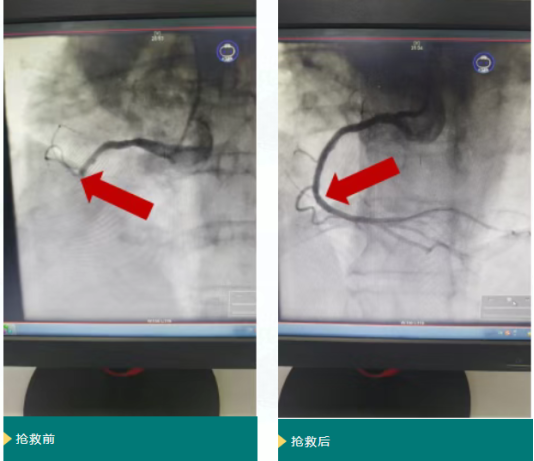

转入后,医院急救绿色通道同步启动,患者直接被推送至导管室行急诊 PCI(经皮冠状动脉介入治疗)。术中患者突发血压、心率持续下降,陷入循环衰竭状态。麻醉与介入团队立即联合抢救:静脉输注多巴胺、去甲肾上腺素维持血压,注射阿托品提升心率,同时快速推进冠脉造影。影像显示患者右冠状动脉自开口完全闭塞,导丝团队精准操作通过闭塞段,于右冠开口植入1枚支架。虽血管近端血流恢复,但远端可见大量血栓影,团队随即实施导管血栓抽吸,并冠脉内注射替罗非班抗栓治疗。